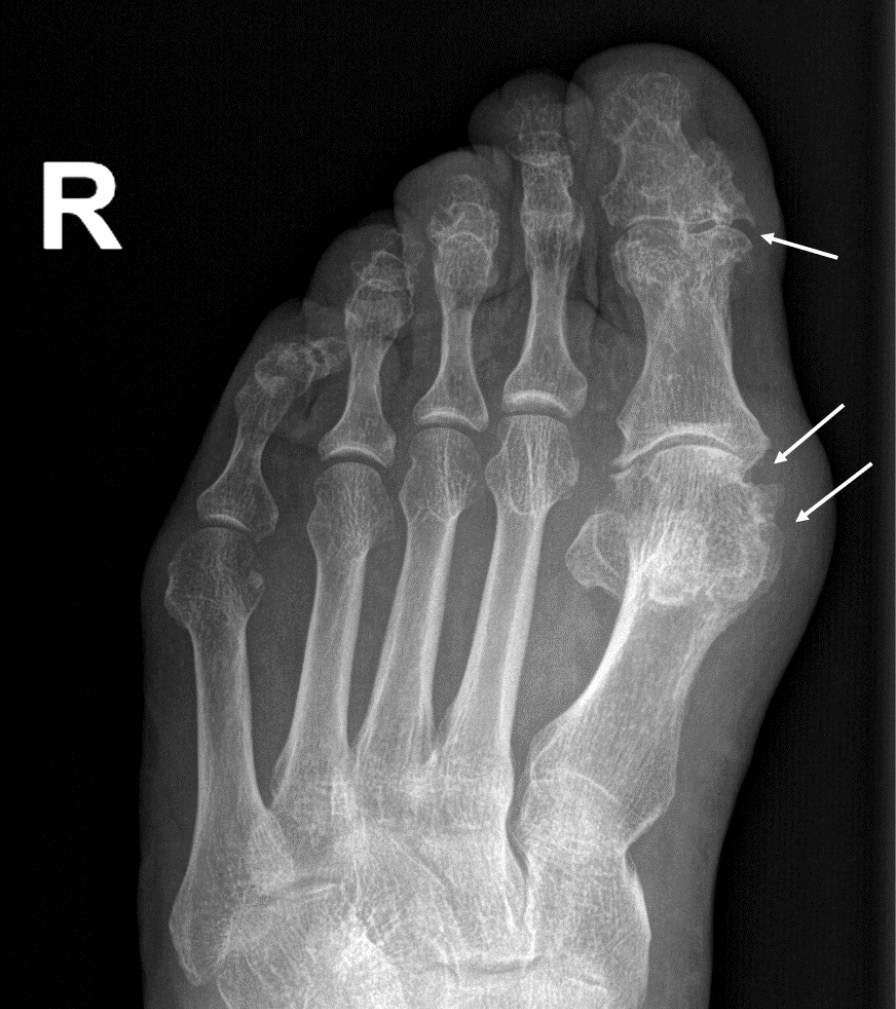

При компьютерной томографии органов грудной клетки данных за «свежие» очаговые и инфильтративные изменения не получено. Увеличения лимфатических узлов подмышечных областей, средостения, корней легких не выявлено. Отмечался усиленный грудной кифоз, обызвествление передней продольной связки, на всем уровне исследования определялись передне-боковые спондилофиты, а также анкилоз большинства реберно-поперечных суставов. По данным рентгенографии кистей (рис. 1, 2) и стоп (рис. 3, 4) диагностированы признаки эрозивного артрита, анкилоз суставов запястья. По данным МРТ крестцово-подвздошных суставов (КПС) определялся неравномерный анкилоз КПС, хрящи по суставным поверхностям неравномерной толщины, примерно на половине протяжении сустава отсутствуют, «суставной промежуток» облитерирован. Неравномерность и нечеткость контура суставных поверхностей за счет множества краевых эрозий справа, единичных – слева, с наличием остеокластоза, в нижнем отделе слева по смежным отделам определяются участки трабекулярного отека, данная находка клинически интерпретирована как двусторонний активный сакроилиит (рис. 5, 6).

Рис. 3. Рентгенограмма правой стопы в прямой проекции. Краевые эрозии суставных поверхностей первого плюсне-фалангового сустава и межфалангового сустава I пальца (стрелки), сужение суставных щелей. Вальгусная деформация I пальца стопы

Рис. 4. Рентгенограмма левой стопы в прямой проекции. Краевые эрозии суставных поверхностей первого плюсне-фалангового сустава (стрелки), сужение суставной щели. Вальгусная деформация I пальца стопы

В возрасте 40 лет присоединились жалобы на симметричные воспалительные боли в лучезапястных суставах и мелких суставах кистей, резкое снижение объема движения в лучезапястных суставах. При осмотре пациента выявлено: число болезненных суставов – 7, число припухших суставов – 4, положительный симптом поперечного сжатия кистей и стоп, ульнарная девиация мелких суставов стоп. Резко сниженный объем движения в лучезапястных суставах обеих кистей. По данным рентгенологического обследования зафиксированы типичные изменения для РА: резкое неравномерное выраженное сужение суставных щелей, субхондральный склероз в лучезапястных суставах, анкилоз в суставах запястья, пястно-запястных, пястно-фаланговых и межфаланговых суставах. Краевые эрозии оснований основных фаланг двух пальцев; участки кистовидной перестройки костной ткани. Локальное утолщение мягких тканей. При лабораторном обследовании пациента отмечен положительный ревматоидный фактор, высокий титр антицитруллинированных антител, повышение острофазовых белков.